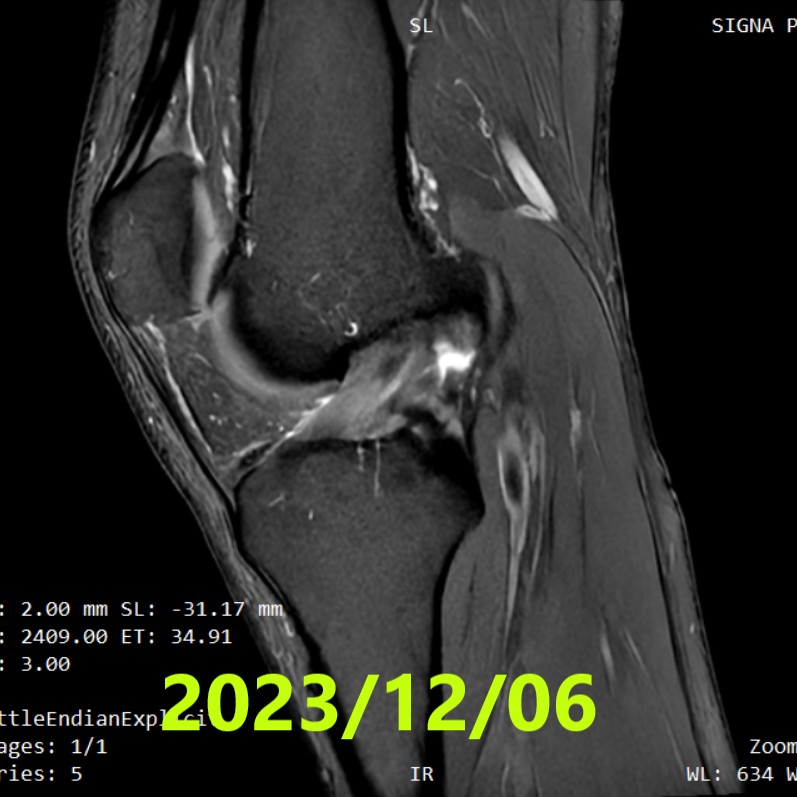

第三次 MRI(最終評估)

- 拍攝日期:2023年12月6日

- 所見:先前觀察到的「鬆弛」消失,確認韌帶恢復了良好的張力。

- 評估:經 3 名獨立影像專家評估,3 名專家全部判定為 ACLOAS 第 1 型(極佳的自然癒合)

- 臨床所見:Lachman 測試陰性

〖ACLOAS(原生前十字韌帶)注釋〗

0 = 正常 / 1 = 伴隨肥厚或高信號,但形態與連續性保存良好(極佳) / 2 = 韌帶變薄、拉長但連續性保存 / 3 = 連續性消失